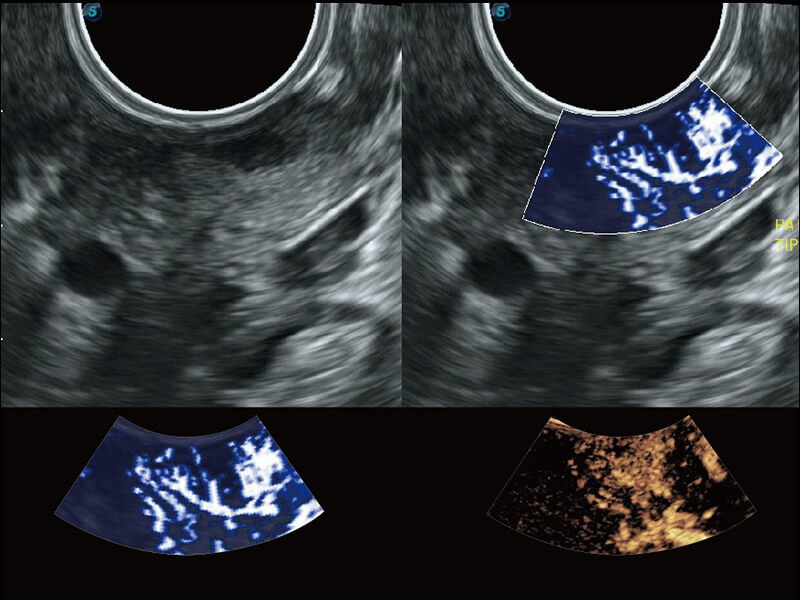

高分辨率容积成像 栩栩如生

超宽频带技术,为容积成像带来优质的二维图像基础,为您呈现丰富的结构细节,栩栩如生地展示宝宝的宫内形态以及各种组织的立体结构。